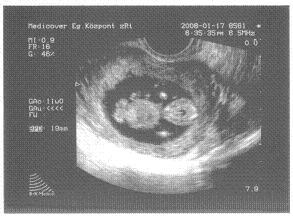

Adataim: első baba, augusztus 17.-re, Kútvölgyibe megyek, ha minden igaz

[img]

[img]